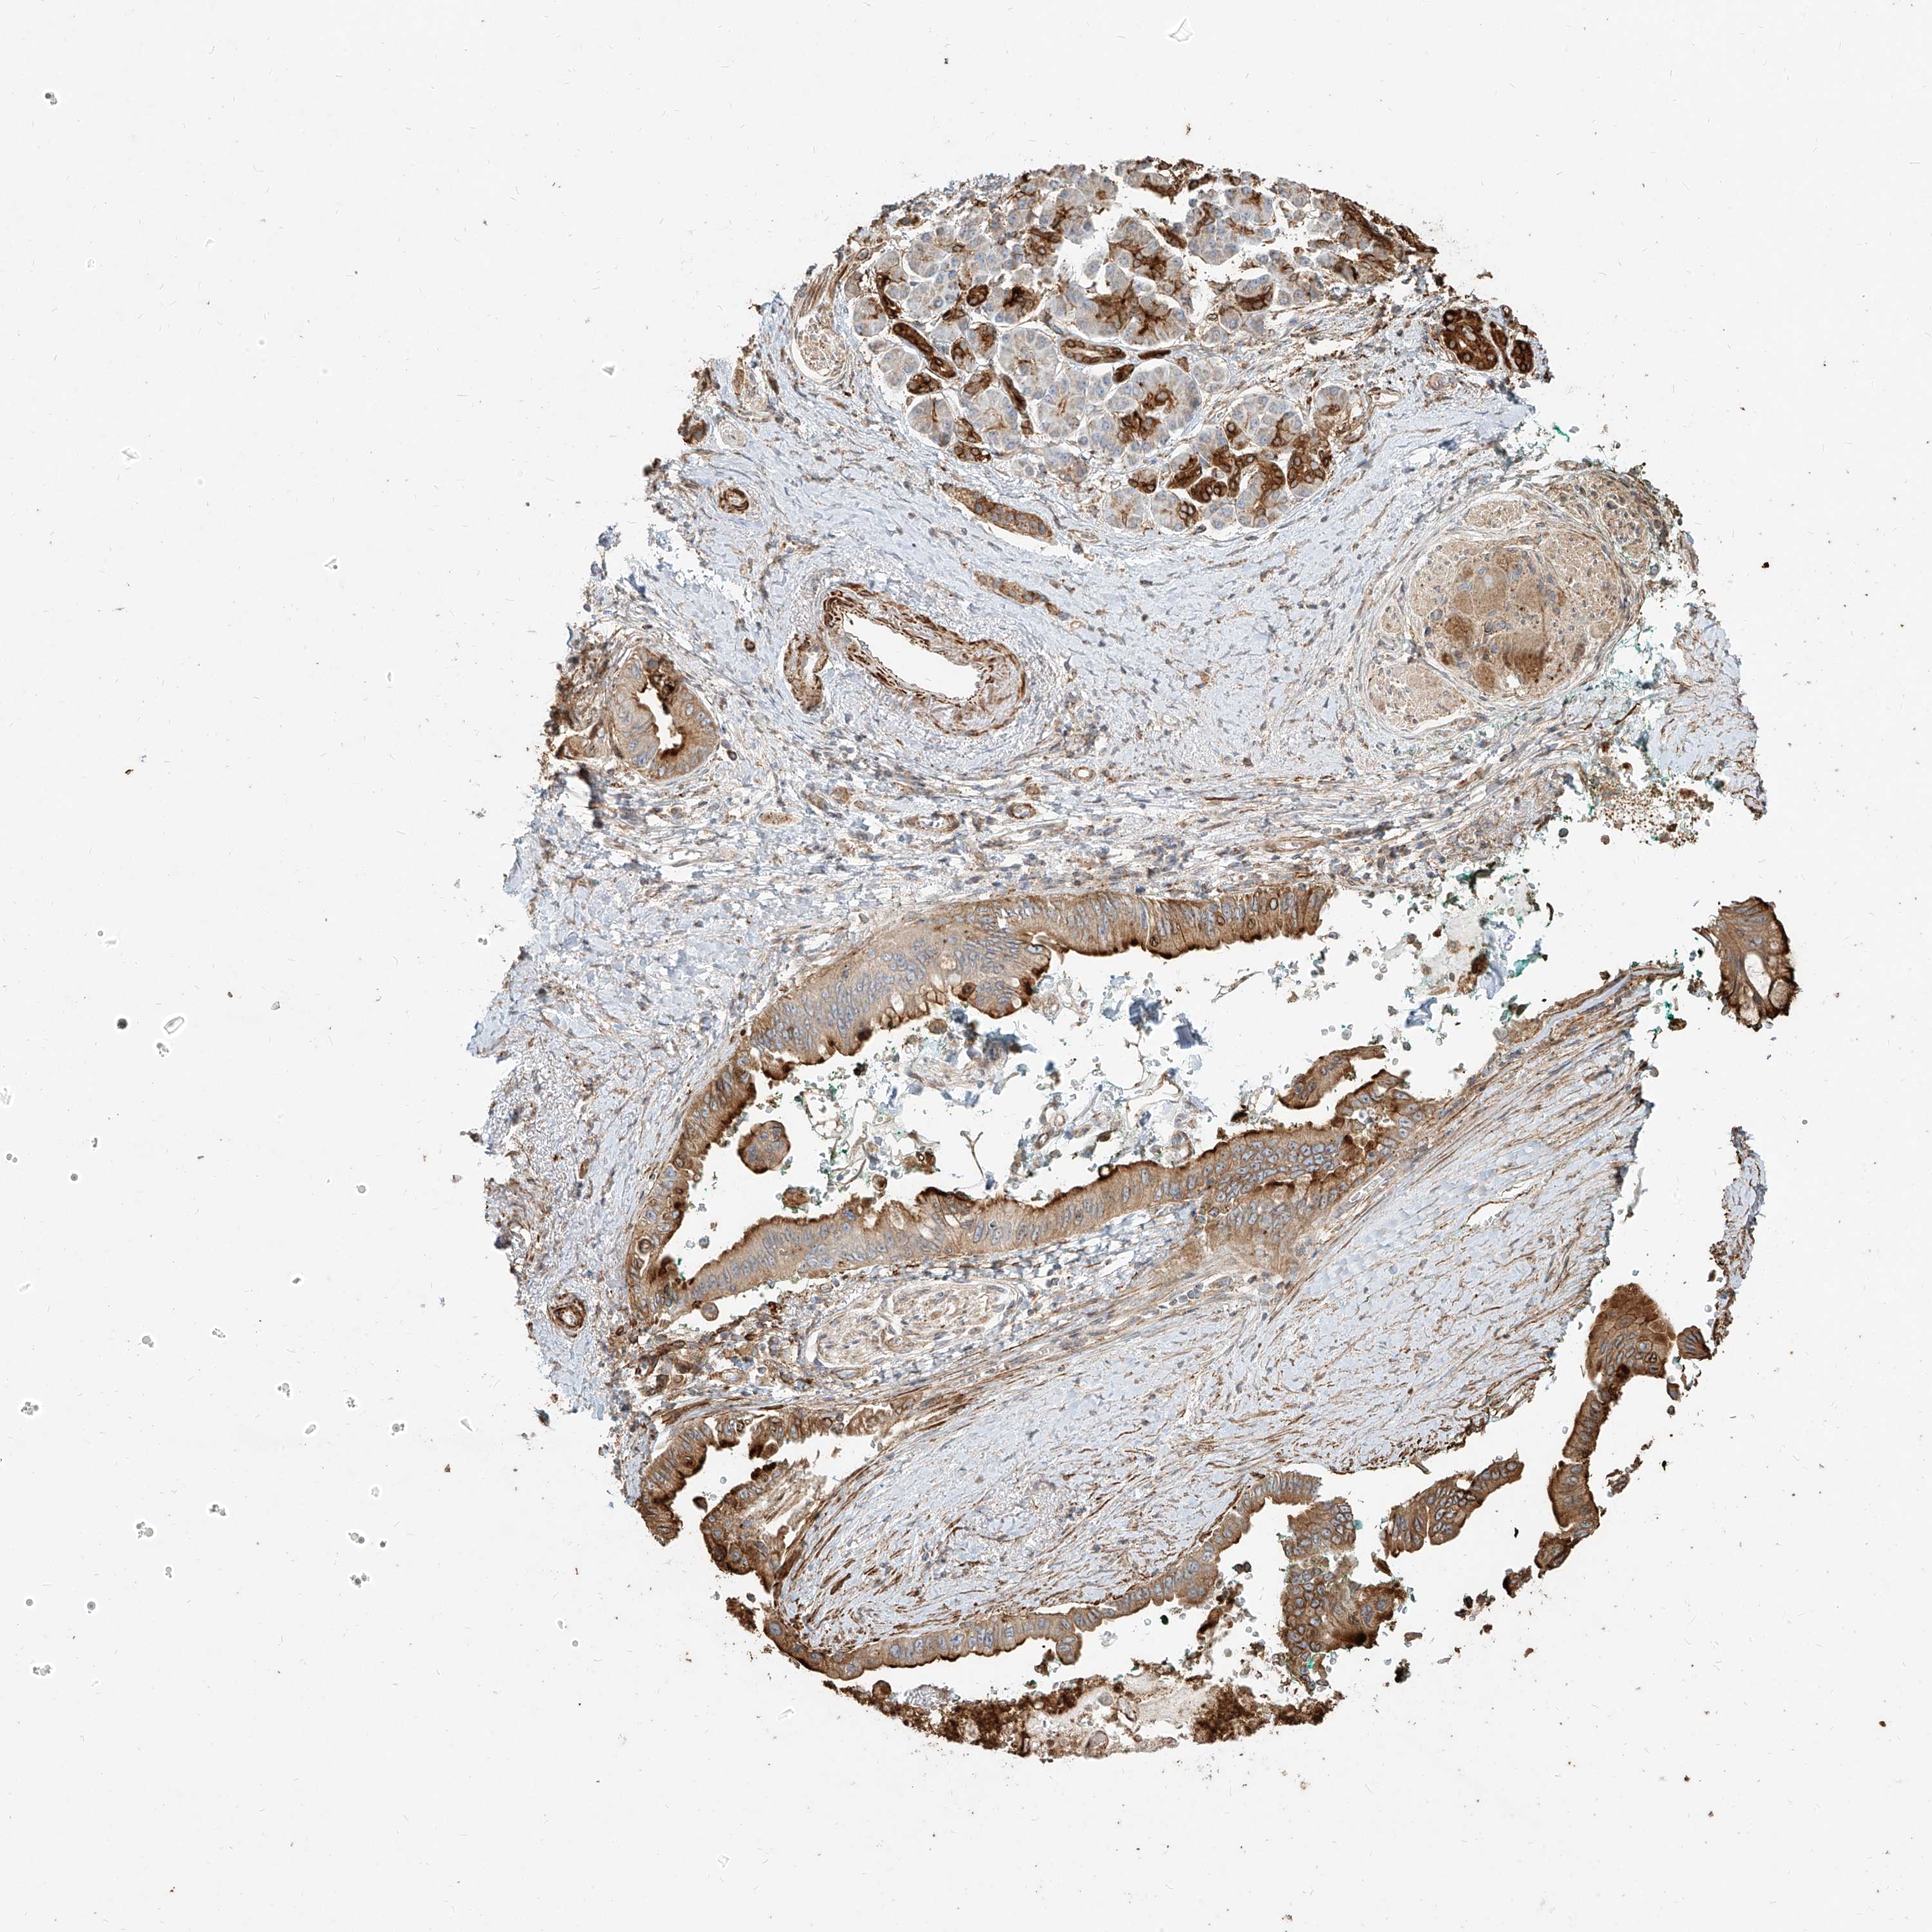

PANCREATIC CANCER - Protein expressioni

A mouse-over function shows sample information and annotation data. Click on an image to view it in a full screen mode. Samples can be filtered based on level of antibody staining by selecting one or several of the following categories: high, medium, low and not detected. The assay and annotation is described here.

Note that samples used for immunohistochemistry by the Human Protein Atlas do not correspond to samples in the TCGA dataset.

Antibody stainingi

Antibody staining in the annotated cell types in the current human tissue is reported as not detected, low, medium, or high, based on conventional immunohistochemistry profiling in selected tissues. This score is based on the combination of the staining intensity and fraction of stained cells.

Each image is clickable and will lead to virtual microscopy that enables deeper exploration of all samples and also displays staining intensity scores, fraction scores and subcellular localization as well as patient and tissue information for each sample.

Antibody HPA031550

Antibody HPA031551

Antibody HPA031552

Staining

High

Medium

Low

Not detected

Intensity

Strong

Moderate

Weak

Negative

Quantity

>75%

75%-25%

<25%

None

Location

Nuclear

Cytoplasmic/membranous

Cytoplasmic/membranous,nuclear

Adenocarcinoma, NOS